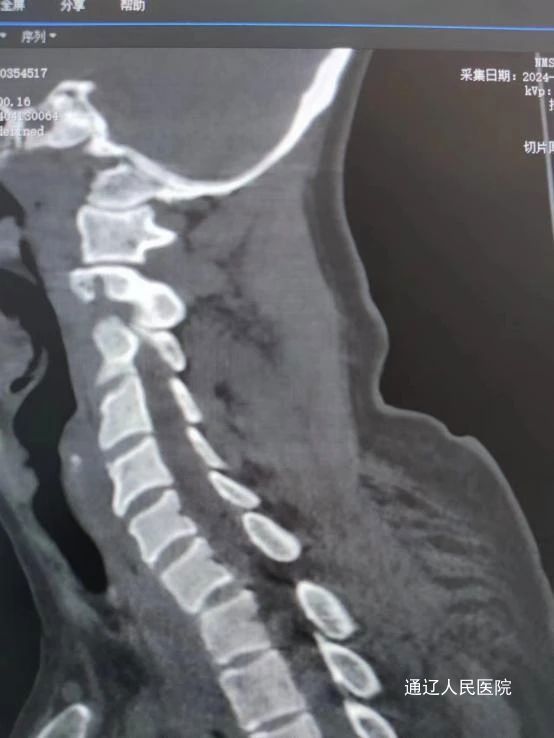

近日,我院脊柱外科在科室负责人房芳的带领下成功为一名颈7椎体骨折脱位合并截瘫的患者,施行了后入路颈椎骨折脱位切开复位减压植骨、颈椎侧块螺钉内固定、胸椎椎弓根螺钉内固定术,这项手术在骨科领域被认为是“三高”手术,即高难度、高风险、高要求,填补了我市技术空白。患者女性,68岁,因外伤致颈7椎体骨折脱位合并截瘫,由下级医院转院送至我院治疗。入院后,医院领导高度重视,迅速进行资源调配,保障及时抢救。我院医护团队立即展开积极对症处理措施,并迅速完善相关检查。考虑到患者年龄较大且病情严重,医务部组织了重症监护和麻醉团队等多学科开展联合会诊MDT。经过深入讨论和分析,专家们为患者量身定制了详尽的手术治疗方案,旨在最大限度地降低手术风险,确保患者安全。

术中减压充分、颈椎骨折脱位完全复位,内固定位置及牢固程度令人满意。在我院脊柱外科、手术室、麻醉科、ICU、输血科协力合作下手术顺利完成。术后患者生命体征平稳,双下肢感觉部分恢复。肢体可以活动。恢复康复训练后远期可生活自理。

颈胸交界处固定手术对于脊柱外科一直属于一个难点,由于在较小的颈椎和较大的胸段交界处有不同的过渡应力,靠近神经血管结构,以及复杂的解剖结构,在固定这些区域时必须极其小心和精确。作为通辽市首例颈椎胸椎联合固定手术,这项手术的成功实施,不仅体现了我院脊柱外科医生的精湛技艺,也为脊柱疾病患者带来了新的治疗希望,标志着我院脊柱外科在颈椎、高位胸椎疾病治疗方面,上了一个新的台阶。随着医学技术的不断进步,我院将不断引进和学习国际先进的医疗技术和理念,提升诊疗水平。同时,加强与国内知名医疗机构的合作,共同推动脊柱外科领域的发展,为患者健康保驾护航。